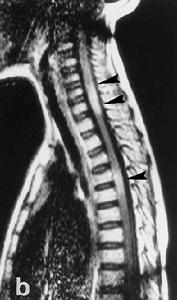

2.MRI的敏感性較高急性期患者於T2加權圖像上可見高密度影,而於T1加權圖像上則為等密度或低密度影。多呈圓形、線形、新月形或不規則形勱主要分布於腦幹。特別是中腦的大腦腳和腦橋周圍此外,勱在丘腦基底核、大腦半球脊髓及小腦等部位也可發現類似異常信號影病情嚴重時,還可見到水腫帶和占位效應。反覆發作的慢性NBD患者,晚期可見到腦幹萎縮。